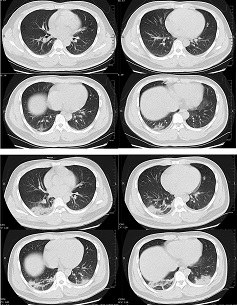

Аномальные результаты КТ органов грудной клетки были зафиксированы у 97% госпитализированных пациентов.[616] Самыми распространенными находками являются поражения по типу матового стекла – как отдельно, так и в сочетании с другими находками, в частности уплотнением, утолщением междолевой перегородки или картины «булыжной мостовой». Наиболее распространенной картиной является двустороннее, периферическое/субплевральное затемнение и затемнение задних участков с преобладанием поражения нижних долей. У пациентов пожилого возраста и пациентов с тяжелым заболеванием чаще наблюдаются обширные/мультилобарные поражения с уплотнениями. К атипичным проявлениям относят расширение легочных сосудов, утолщение междолевых или внутридолевых перегородок, утолщение прилегающей плевры, воздушные бронхограммы, субплевральные линии, картина по типу «булыжной мостовой», искривление бронхов, бронхоэктазы, признак вакуумной ретракции и признак ореола. Также редко наблюдались выпот в плевральной полости, перикардиальный выпот, кавитации, пневмоторакс и медиастинальная лимфаденопатия.[617] Затемнение по типу матового стекла имеет наибольшую диагностическую ценность при пневмонии, вызванной COVID-19, за ним следует затемнение по типу матового стекла плюс уплотнение и уплотнение отдельно.[618]

КТ как правило показывает увеличение размера, количества и плотности затмений по типу матового стекла на раннем этапе наблюдения, после чего наблюдается прогрессирование к смешанным участкам затмений по типу матового стекла, уплотнений и картины "булыжной мостовой" с пиком на 10-11 день, а затем поражения постепенно исчезают или персистируют в виде пятнистого фиброза.[617]

КТ более чувствительна, чем ПЦР с обратной транскрипцией, при обнаружении COVID-19, но имеет очень низкую специфичность.[733] В когорте из более 1000 пациентов в гиперэндемичном регионе Китая КТ органов грудной клетки имела более высокую чувствительность для диагностики COVID-19 по сравнению с начальной ПЦР-ОТ образцов мазка (88% в сравнении с 59%). Улучшение картины КТ также предшествовало изменению позитивного результата ПЦР-ОТ на негативный в этой когорте пациентов во время выздоровления. Чувствительность КТ органов грудной клетки составила 97% у пациентов, которые в конечном итоге имели положительные результаты ПЦР-ОТ. Однако в этом случае у 75% пациентов с отрицательными результатами ПЦР-ОТ также отмечались положительные признаки на КТ органов грудной клетки. Из этих пациентов 48% рассматривались как наиболее вероятные случаи, в то время как 33% – как возможные случаи.[734][Figure caption and citation for the preceding image starts]: Поперечная компьютерная томография 32-летнего мужчины показывает затемнение по типу матового стекла и уплотнение в нижней доле правого легкого возле плевры в 1-й день после появления симптомов (верхний снимок), а также двусторонние затемнения и консолидацию по типу матового стекла на 7-й день после появления симптомов [Citation ends].